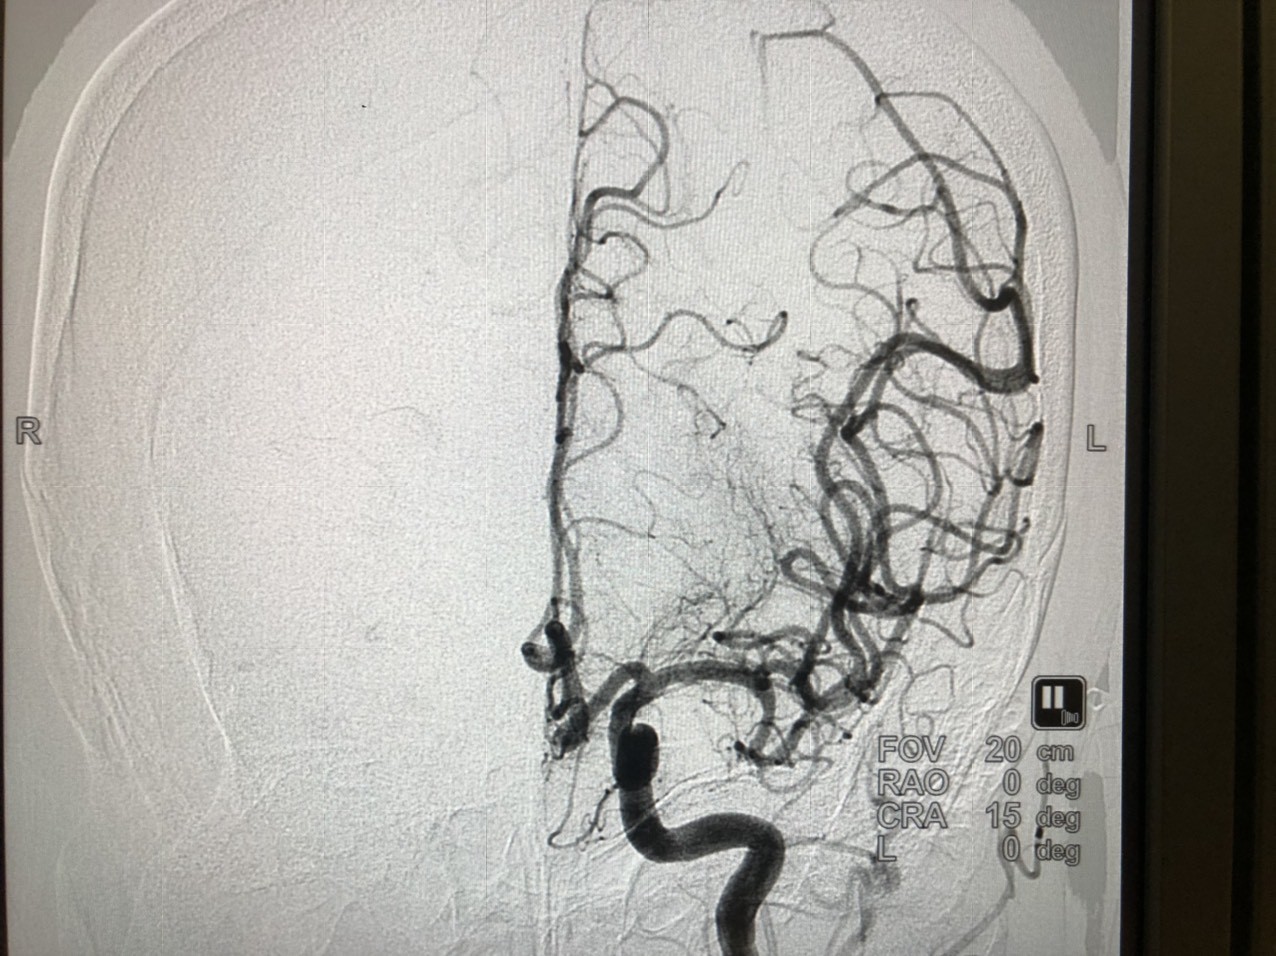

![]() |

| Hình sau khi lấy cục huyết khối ra và mạch máu đã đc tái thông |